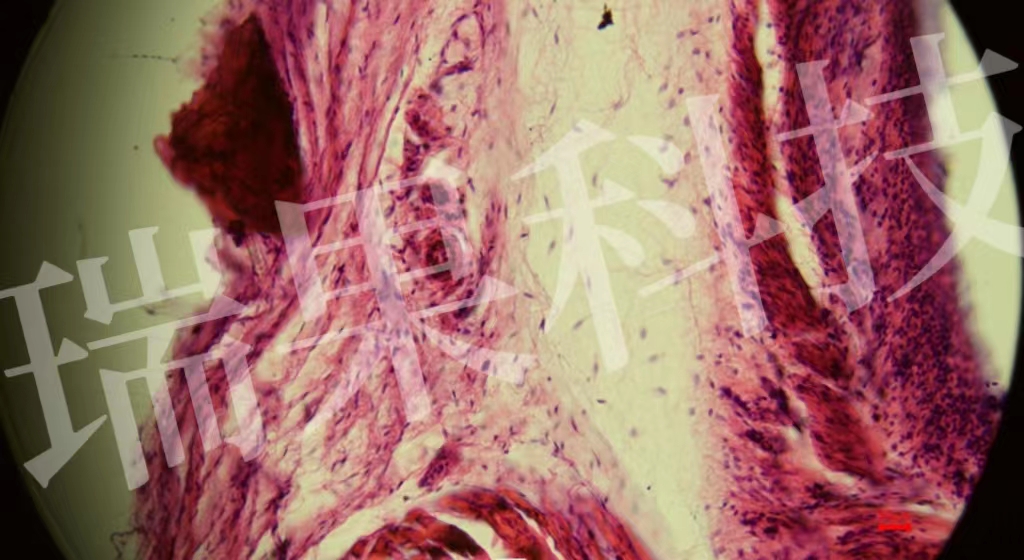

HE染色:蘇木精 - 伊紅染色法 ( hematoxylin-eosin staining ) ,簡(jiǎn)稱(chēng)HE染色法 ,石蠟切片技術(shù)里常用的染色法之一 。蘇木精染液為堿性 ,主要使細(xì)胞核內(nèi)的染色質(zhì)與胞質(zhì)內(nèi)的核酸著紫藍(lán)色 ;伊紅為酸性染料 ,主要使細(xì)

HE染色:蘇木精 - 伊紅染色法 ( hematoxylin-eosin staining ) ,簡(jiǎn)稱(chēng)HE染色法 ,石蠟切片技術(shù)里常用的染色法之一 。蘇木精染液為堿性 ,主要使細(xì)胞核內(nèi)的染色質(zhì)與胞質(zhì)內(nèi)的核酸著紫藍(lán)色 ;伊紅為酸性染料 ,主要使細(xì)胞質(zhì)和細(xì)胞外基質(zhì)中的成分著紅色 。HE染色法是組織學(xué)、胚胎學(xué)、病理學(xué)教學(xué)與科研中最基本、使用最廣泛的技術(shù)方法。

視網(wǎng)膜

心1-1-20x

血清粘液腺-20x